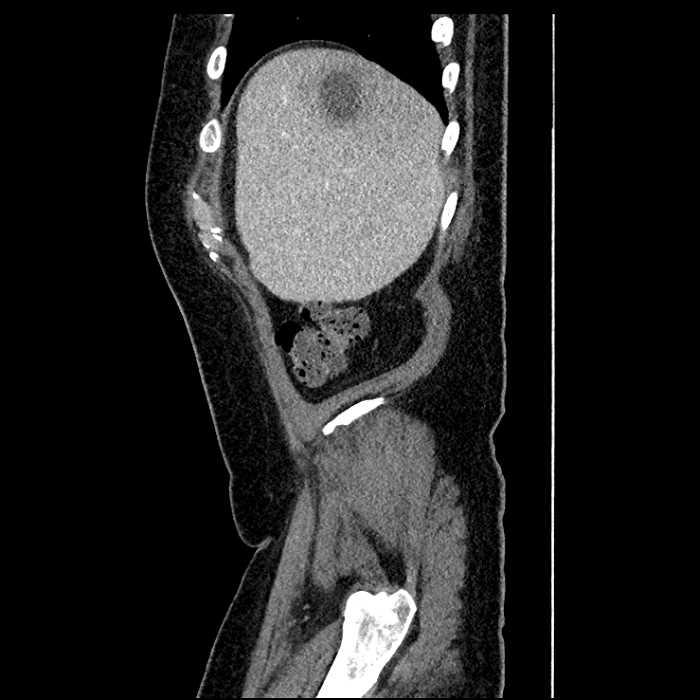

• Large fluid density structure in hepatic segments 7 and 8 measuring 10 x 7 x 7 cm with internal septation and circumferential ill-defined low density compatible with edema

• Hepatic abscess

Acute sigmoid diverticulitis complicated by a small contained perforation and a large abscess in the right hepatic lobe. Additional small subcapsular abscesses along the anterior margin of the left hepatic lobe.

• The classic CT imaging appearance is a double target sign with internal low density surrounded by an internal enhancing rim (capsule) and a low density external rim (edema)

• Abscesses may be unilocular or multilocular

Hepatic abscess showing the double target sign with low density internally surrounded by a thin inner enhancing rim (red arrow) and ill-defined outer low density rim (yellow arrow). Blue arrow indicates an internal septation. Red arrows: additional smaller subcapsular abscesses. Red arrow: focal contained perforation associated with diverticulitis.